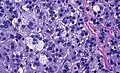

Zona fasciculata versus adrenocortical adenoma. An adrenocortical adenoma typically has mild changes in comparison, including larger cells with larger and more pleomorphic nuclei with more coarse chromatin. H&E stain.

The microscopic histopathology analysis of the tissue samples obtained from the adrenal cortex of individuals presenting with adenoma-associated symptoms such as primary aldestronism (PA) indicates that adenoma cells are relatively larger with different cytoplasm, and increased variation in nuclear size. This indication is based on comparison between the healthy (normal) and affected (adenoma-associated) adrenal cortex tissue samples.